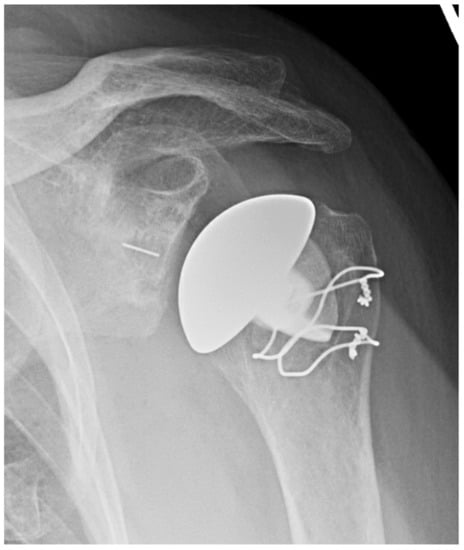

3.2.2. Inlay vs. Onlay Implants